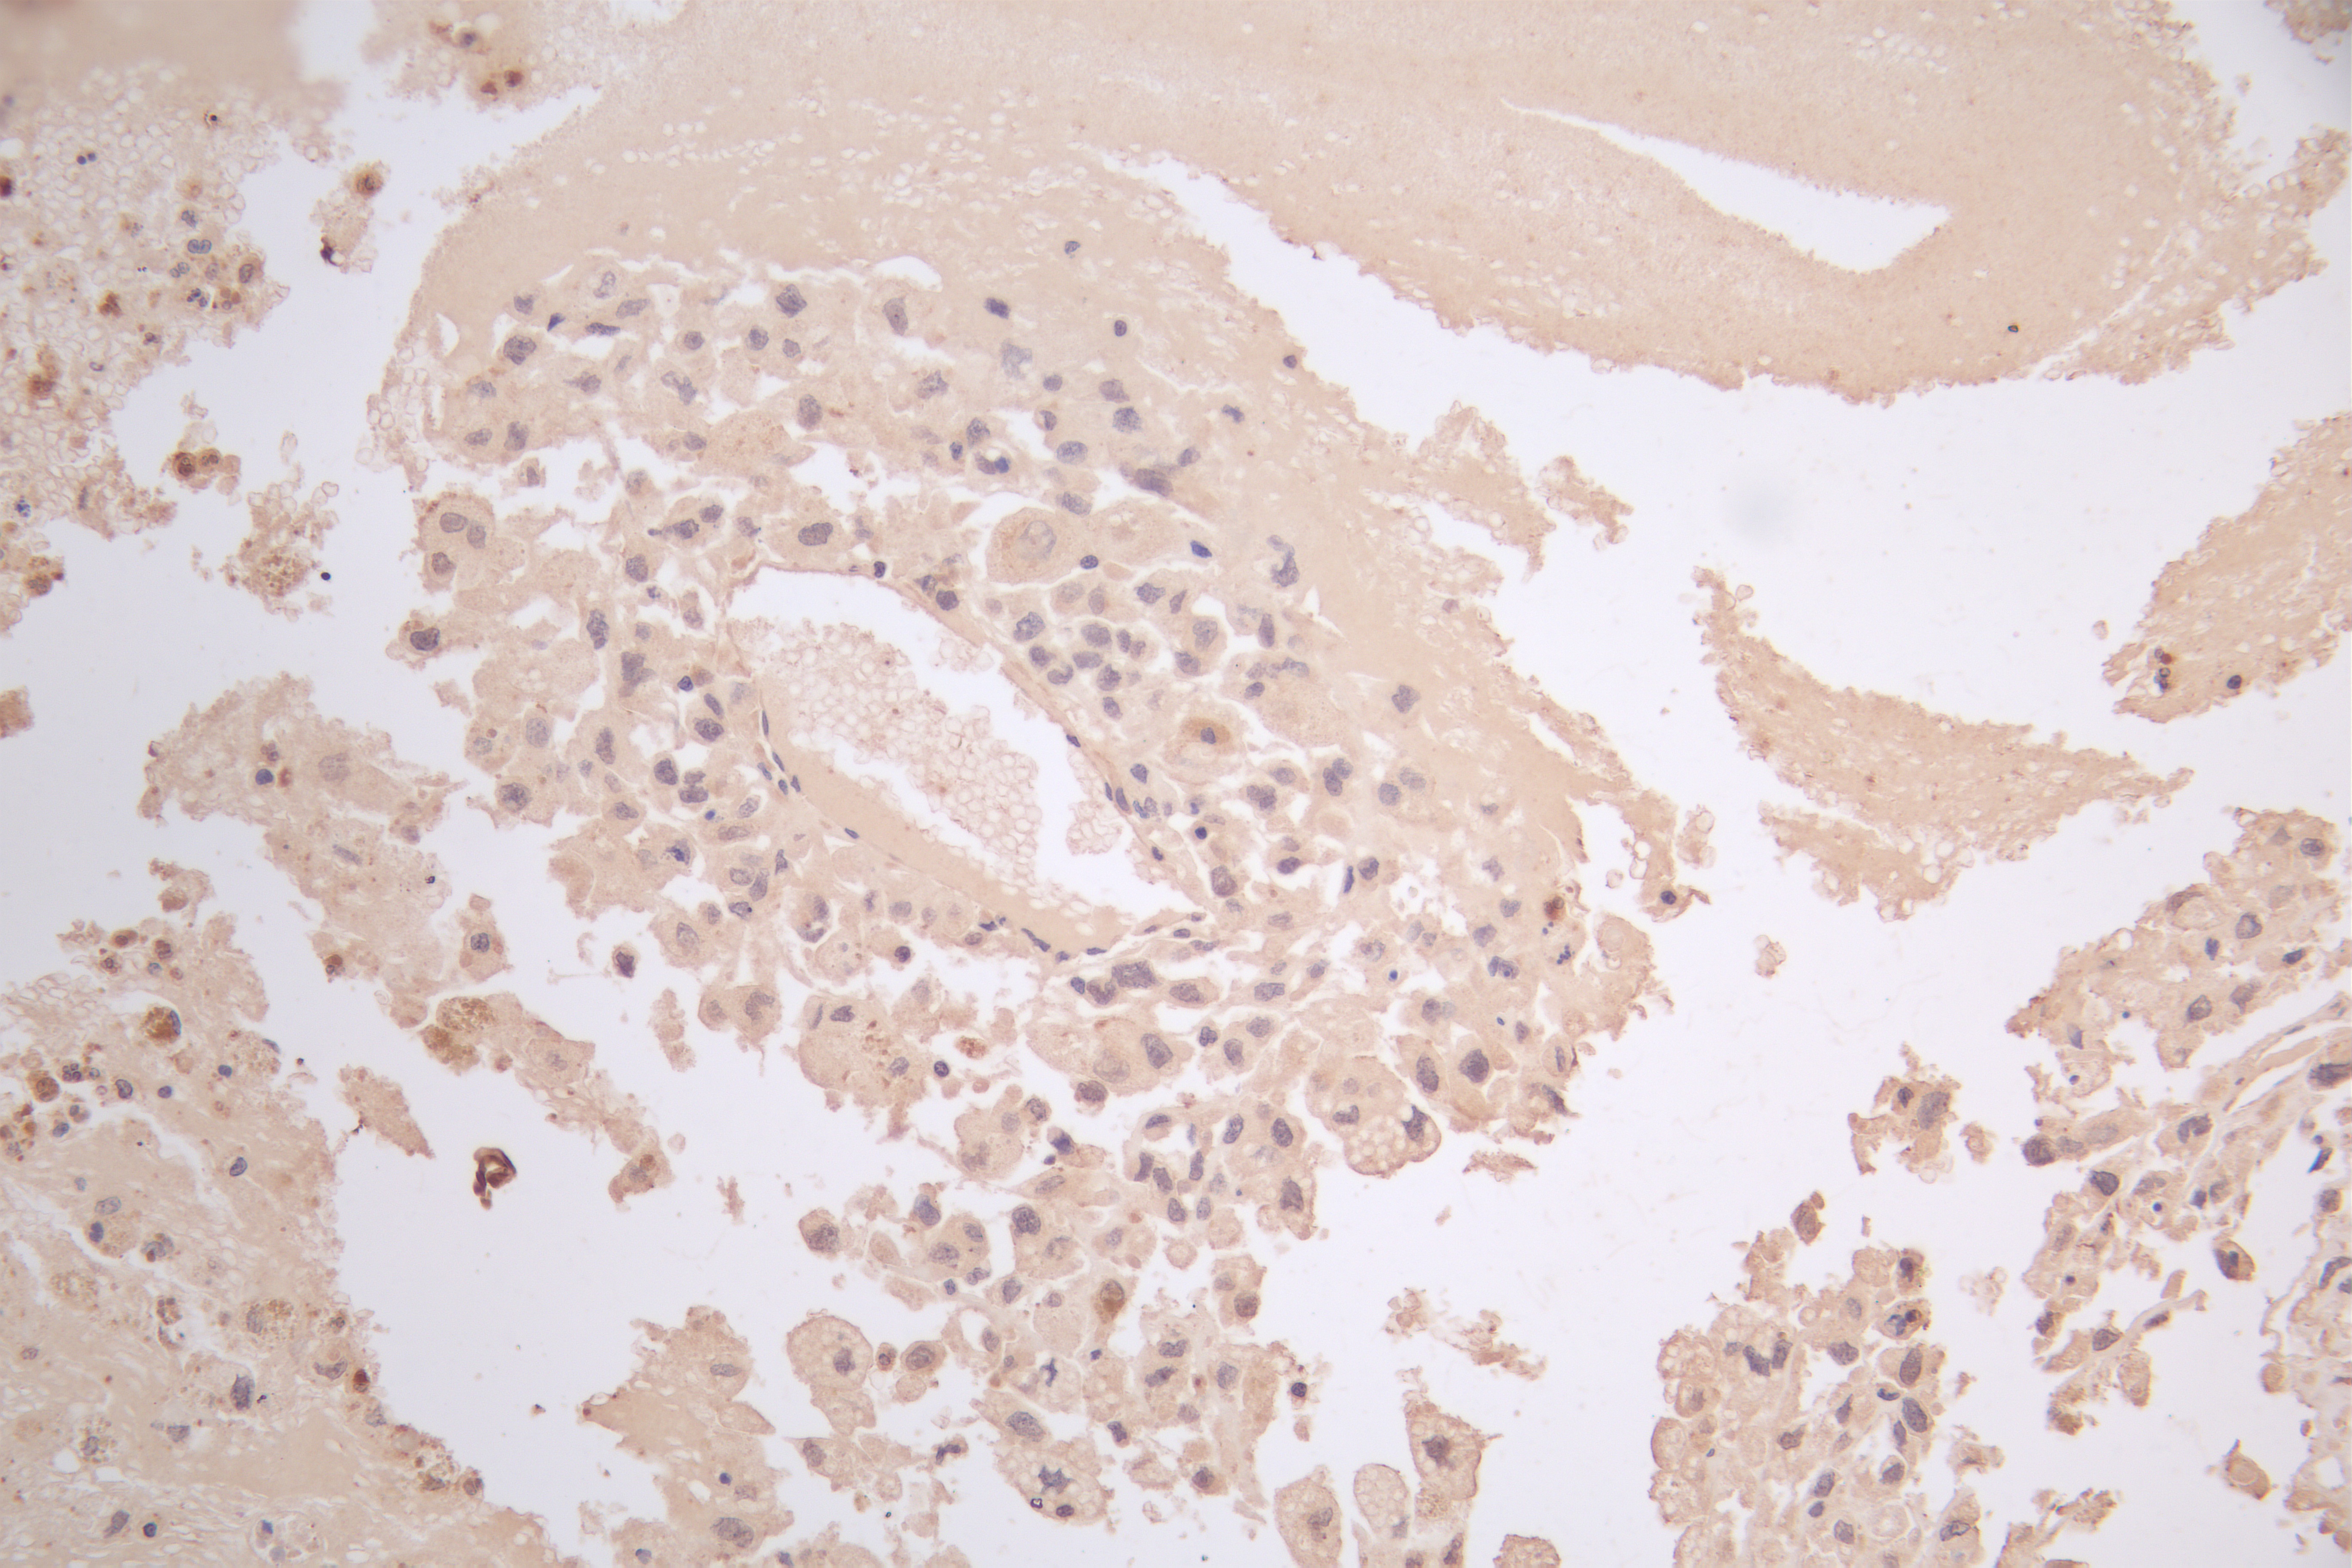

IHC image of CSB-PA002657 diluted at 1:66 and staining in paraffin-embedded human melanoma cancer performed on a Leica BondTM system. After dewaxing and hydration, antigen retrieval was mediated by high pressure in a citrate buffer (pH 6.0). Section was blocked with 10% normal goat serum 30min at RT. Then primary antibody (1% BSA) was incubated at 4°C overnight. The primary is detected by a Goat anti-rabbit polymer IgG labeled by HRP and visualized using 0.05% DAB.